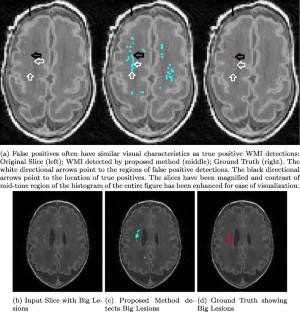

White matter injury (WMI) is the most prevalent brain injury in the preterm neonate leading to developmental deficits. However, detecting WMI in magnetic resonance (MR) images of preterm neonate brains using traditional WM segmentation-based methods is difficult mainly due to lack of reliable preterm neonate brain atlases to guide segmentation. Hence, we propose a segmentation-free, fast, unsupervised, atlas-free WMI detection method. We detect the ventricles as blobs using a fast linear maximally stable extremal regions algorithm. A reference contour equidistant from the blobs and the brain-background boundary is used to identify tissue adjacent to the blobs. Assuming normal distribution of the gray-value intensity of this tissue, the outlier intensities in the entire brain region are identified as potential WMI candidates. Thereafter, false positives are discriminated using appropriate heuristics. Experiments using an expert-annotated dataset show that the proposed method runs 20 times faster than our earlier work which relied on time-consuming segmentation of the WM region, without compromising WMI detection accuracy.

Fig. 1